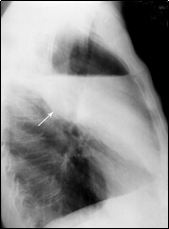

По-прежнему базовым методом подтверждения клинического диагноза бактериальной деструкции легкого остается полипозиционная рентгеноскопия и рентгенография грудной клетки, позволяющая подтвердить диагноз и определить локализацию процесса. При остром абсцессе легкого до сообщения его с бронхиальным деревом определяется правильная округлая гомогенно затемненная полость с перифокальной инфильтрацией (рис. 1). После опорожнения гнойника в дыхательные пути – полость с уровнем жидкости (рис. 2).

Рис. 1. Блокированный абсцесс средней доли правого легкого (отмечен стрелкой). Рентгенограмма грудной клетки в прямой (а) и правой (б) боковой проекции.

б

а